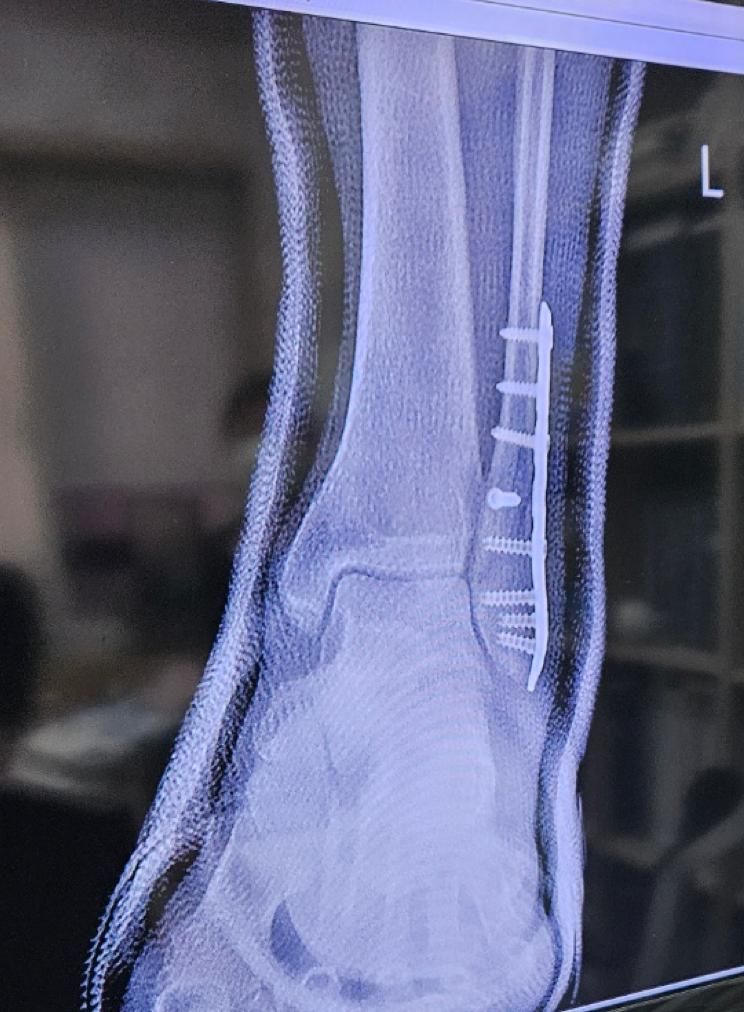

• 3번 째 사진

엑스레이 영상으로 추정컨데, 수상 당시 골절이 심각한 상태였을거라 예상됩니다.

그만큼의 골절이 생겼다면 신경 손상이 동반되었을 가능성이 높고, 이에 대한 회복에는 상당 시간이 소요됩니다.

깁스를 하다가 제거한지 얼마 안되었다면 아직은 회복하는 과정에서 나타나는 증상일거라 사료됩니다.

그러나 이는 골절과 수술 후 생길 수 있는 일반적인 상황에 대해 말씀드리는 바이며, 질문자께서 언급하신 중대 합병증의 가능성도 항상 고려해야 하므로 병원에서 정기적인 관찰과 치료가 유지되어야 합니다.